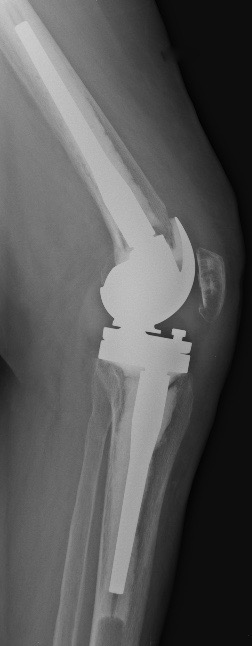

C. PTG de révision

Si faiblesse des ligaments latéraux

Si grandes déformations ou changements de prothèse

quilles d’extension dans le fémur et le tibia pour mieux répartir ces contraintes